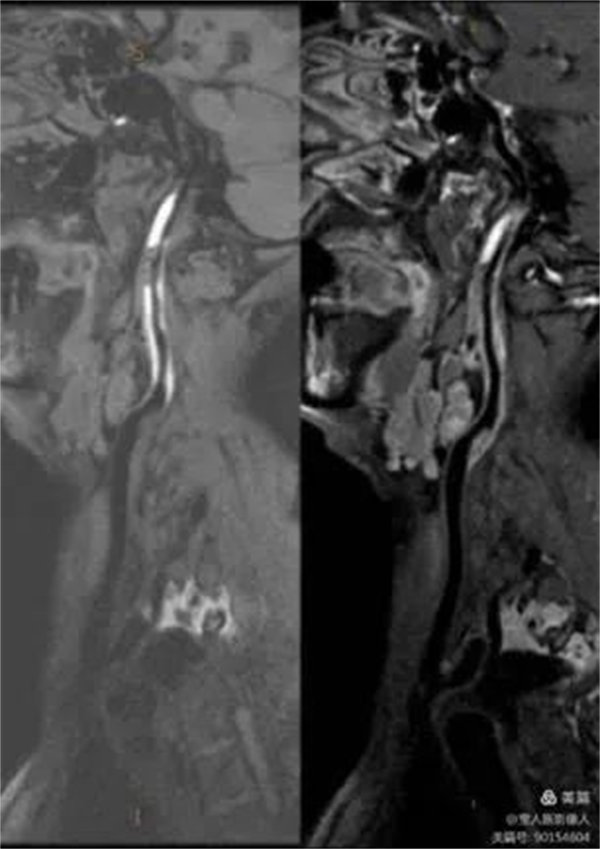

48岁的一名男性患者因长期头痛行颅脑MRI检查,有病变提示,遂进一步行头颈部血管增强磁共振成像(CE-MRA)和血管壁成像(HR-VWI),诊断为颈内动脉颅外段壁间血肿。

HR-VWI管壁明显增厚,呈高信号

HR-VWI管壁增厚,呈新月形高信号

患者行CE-MRA、HR-VWI检查能清晰显示头颈部血管腔、血管壁及脑实质,完美显示动脉瘤和评估动脉瘤稳定性。

血管壁曲面重建显示血管壁,管腔及周围组织结构清晰